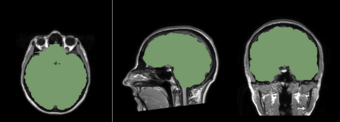

Atlas Image

Atlas Mask

Mask overlay on patient volume